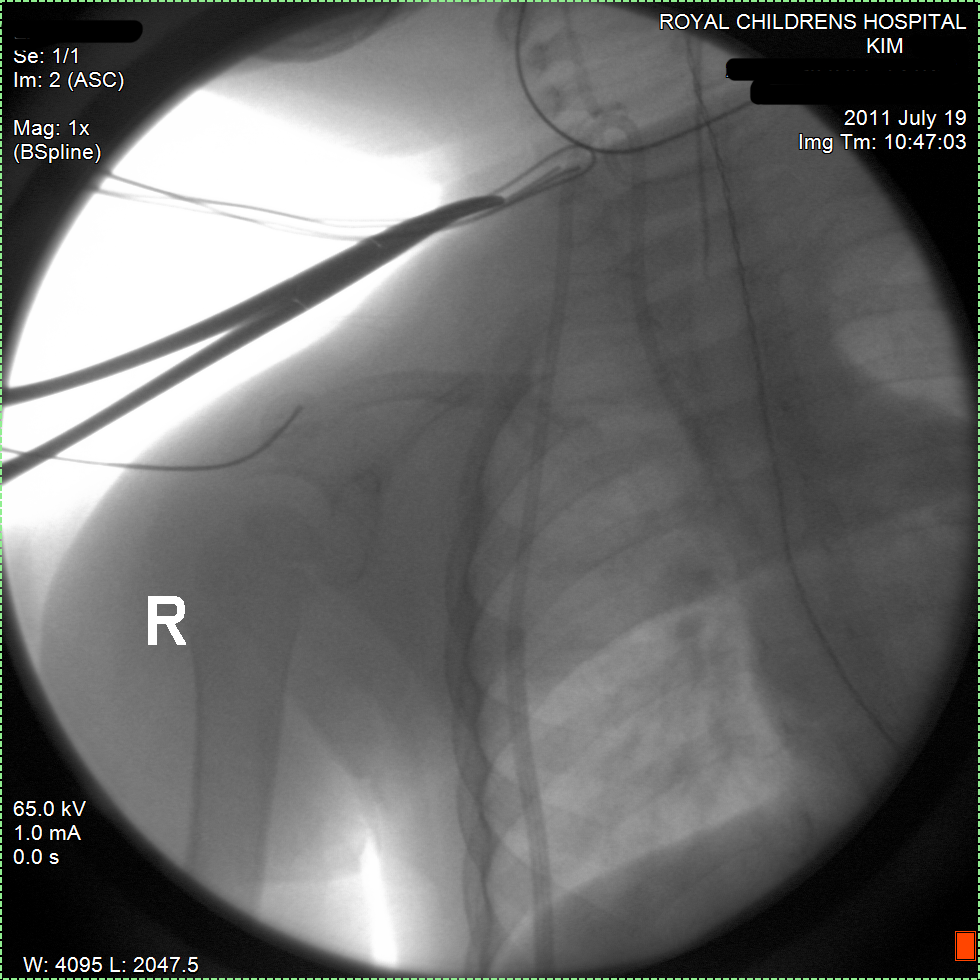

Biopsy of mass, bone marrow aspiration and Hickman catheter surgery. Finally done, but now the samples are going to Pathology (laboratory).

Fasted for surgical biopsy of mass and bone marrow aspiration (taken samples of the cancer and her bone marrow).

Also a Hickman catheter will be surgically implanted. These are tubes that will be put directly into her veins. Through these tubes chemo and medication can be given.